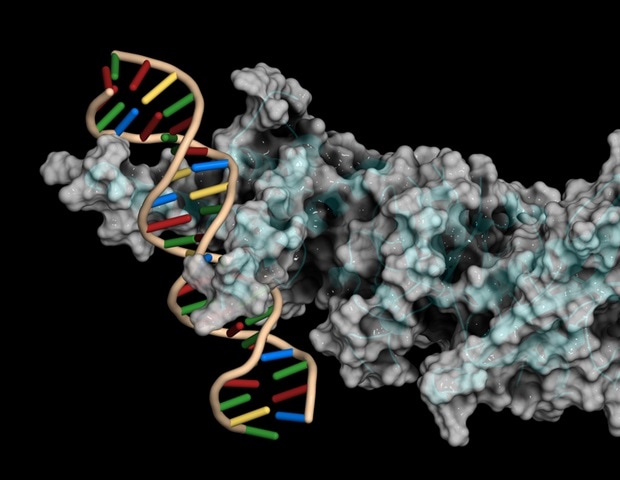

מעכבי פחמן אנהידרז מעכבים הצטברות טאו ברורה בדגמי דג זברה של טאואופתיות

תרופה הנפוצה לטיפול בגלאוקומה הוכחה בדגי זברה ובעכברים כמגינה מפני הצטברות חלבון טאו במוח, הגורמת לצורות שונות של דמנציה ומעורבת

תרופה הנפוצה לטיפול בגלאוקומה הוכחה בדגי זברה ובעכברים כמגינה מפני הצטברות חלבון טאו במוח, הגורמת לצורות שונות של דמנציה ומעורבת